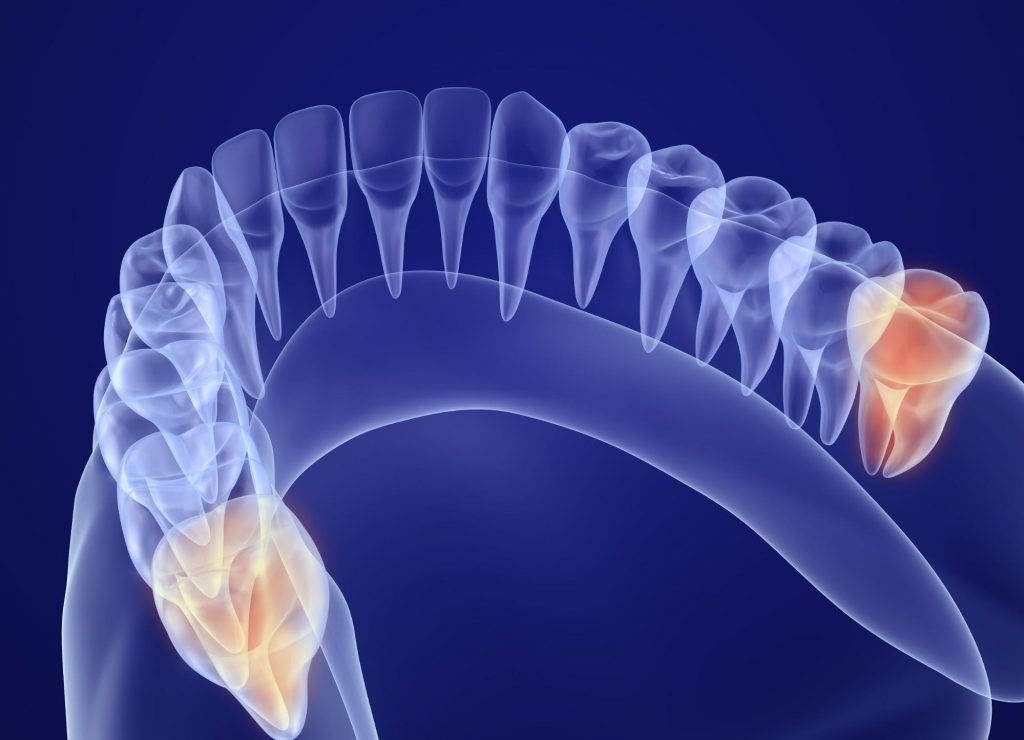

確かに、現代人は昔に比べて顎が小さく、親知らずが歯列にきれいに収まらないケースが増えているため、歯列不正や斜めに生えるなどといったトラブルを起こしてしまう親知らずが増えているのは事実です。

ですが、中には正常にまっすぐ生えている親知らずもありますので、親知らずだからと言って必ずしも抜かなくてはいけないわけではありません。

親知らずが斜めや横向きに生えている場合

また、親知らずが隣の歯を押すことで、歯並びが悪くなったり歯が弱くなったりしてしまう可能性もありますので、将来的にトラブルが予想される親知らずの場合は早めに抜いておくことをおススメします。